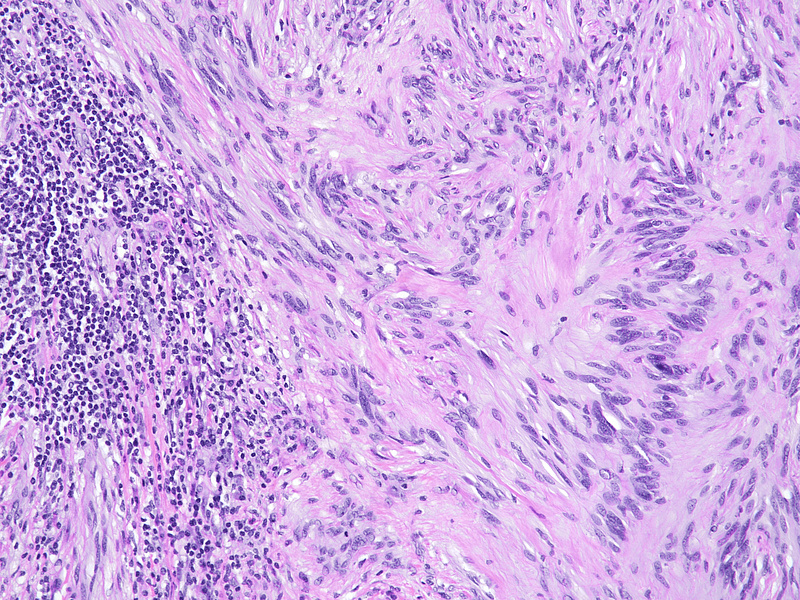

During laparoscopic surgery, the tumour proved to be confined to the appendix, with no other intra-abdominal findings (Panel A). The resection specimen disclosed a well circumscribed solid tumour, 4.2 cm in maximum diameter, with a homogeneously yellowish-white cut surface (Panels B and C).  Histologically, we observed a loose to densely cellular, spindled-cell neoplasia, arranged in fascicular and sweeping patterns (Panel D). Lymphoid aggregates, sometimes forming lymphoid follicles with germinal centres, were  found distributed at the periphery and also throughout the tumour (Panels E and F). The neoplastic cells had sparse cytoplasm and elongated, bland nuclei with inconspicuous nucleoli; focal and moderate atypia was noted (Panel G). Mitotic activity was <5mitoses/10HPF. Haemorrhage or necrosis were not observed. Upon immunohistochemistry, there was diffuse and strong positivity for S100 protein (Panel H) and moderate positivity for GFAP (Panel I). CD117 marked intralesional mast cells, whereas the tumour cells were negative (Panel J). Desmin and smooth muscle actin were negative (not shown).

The characteristic morphology directs to the correct diagnosis: a well-circumscribed lesion, with a marbled appearance due to densely cellular areas alternating with densely cellular areas; and neoplastic spindled cells, sometimes with focal, degenerative atypia. Lymphoid cuffs, usually present in soft tissue schwannomas, have an unclear aetiology; in the appendix, its presence probably is due to remnants of local MALT-tissue. Long fascicular pattern, an epithelioid appearance, tumoral necrosis and increased mitotic activity must raise concern for malignant transformation to MPNST.

Confirmation by immunostaining is required given the mimicry of many mesenchymal tumours and the rarity of appendiceal schwannomas. A characteristic finding is the strong and diffuse positivity for S100 protein. Variable staining for GFAP and CD34 is present. Markers for GIST (CD117, DOG-1) are negative and positivity in Cajal cell hyperplasia or in scattered intralesional mastocytes is an important pitfall to consider. Also, muscle markers (desmin, smooth muscle actin) must be negative.